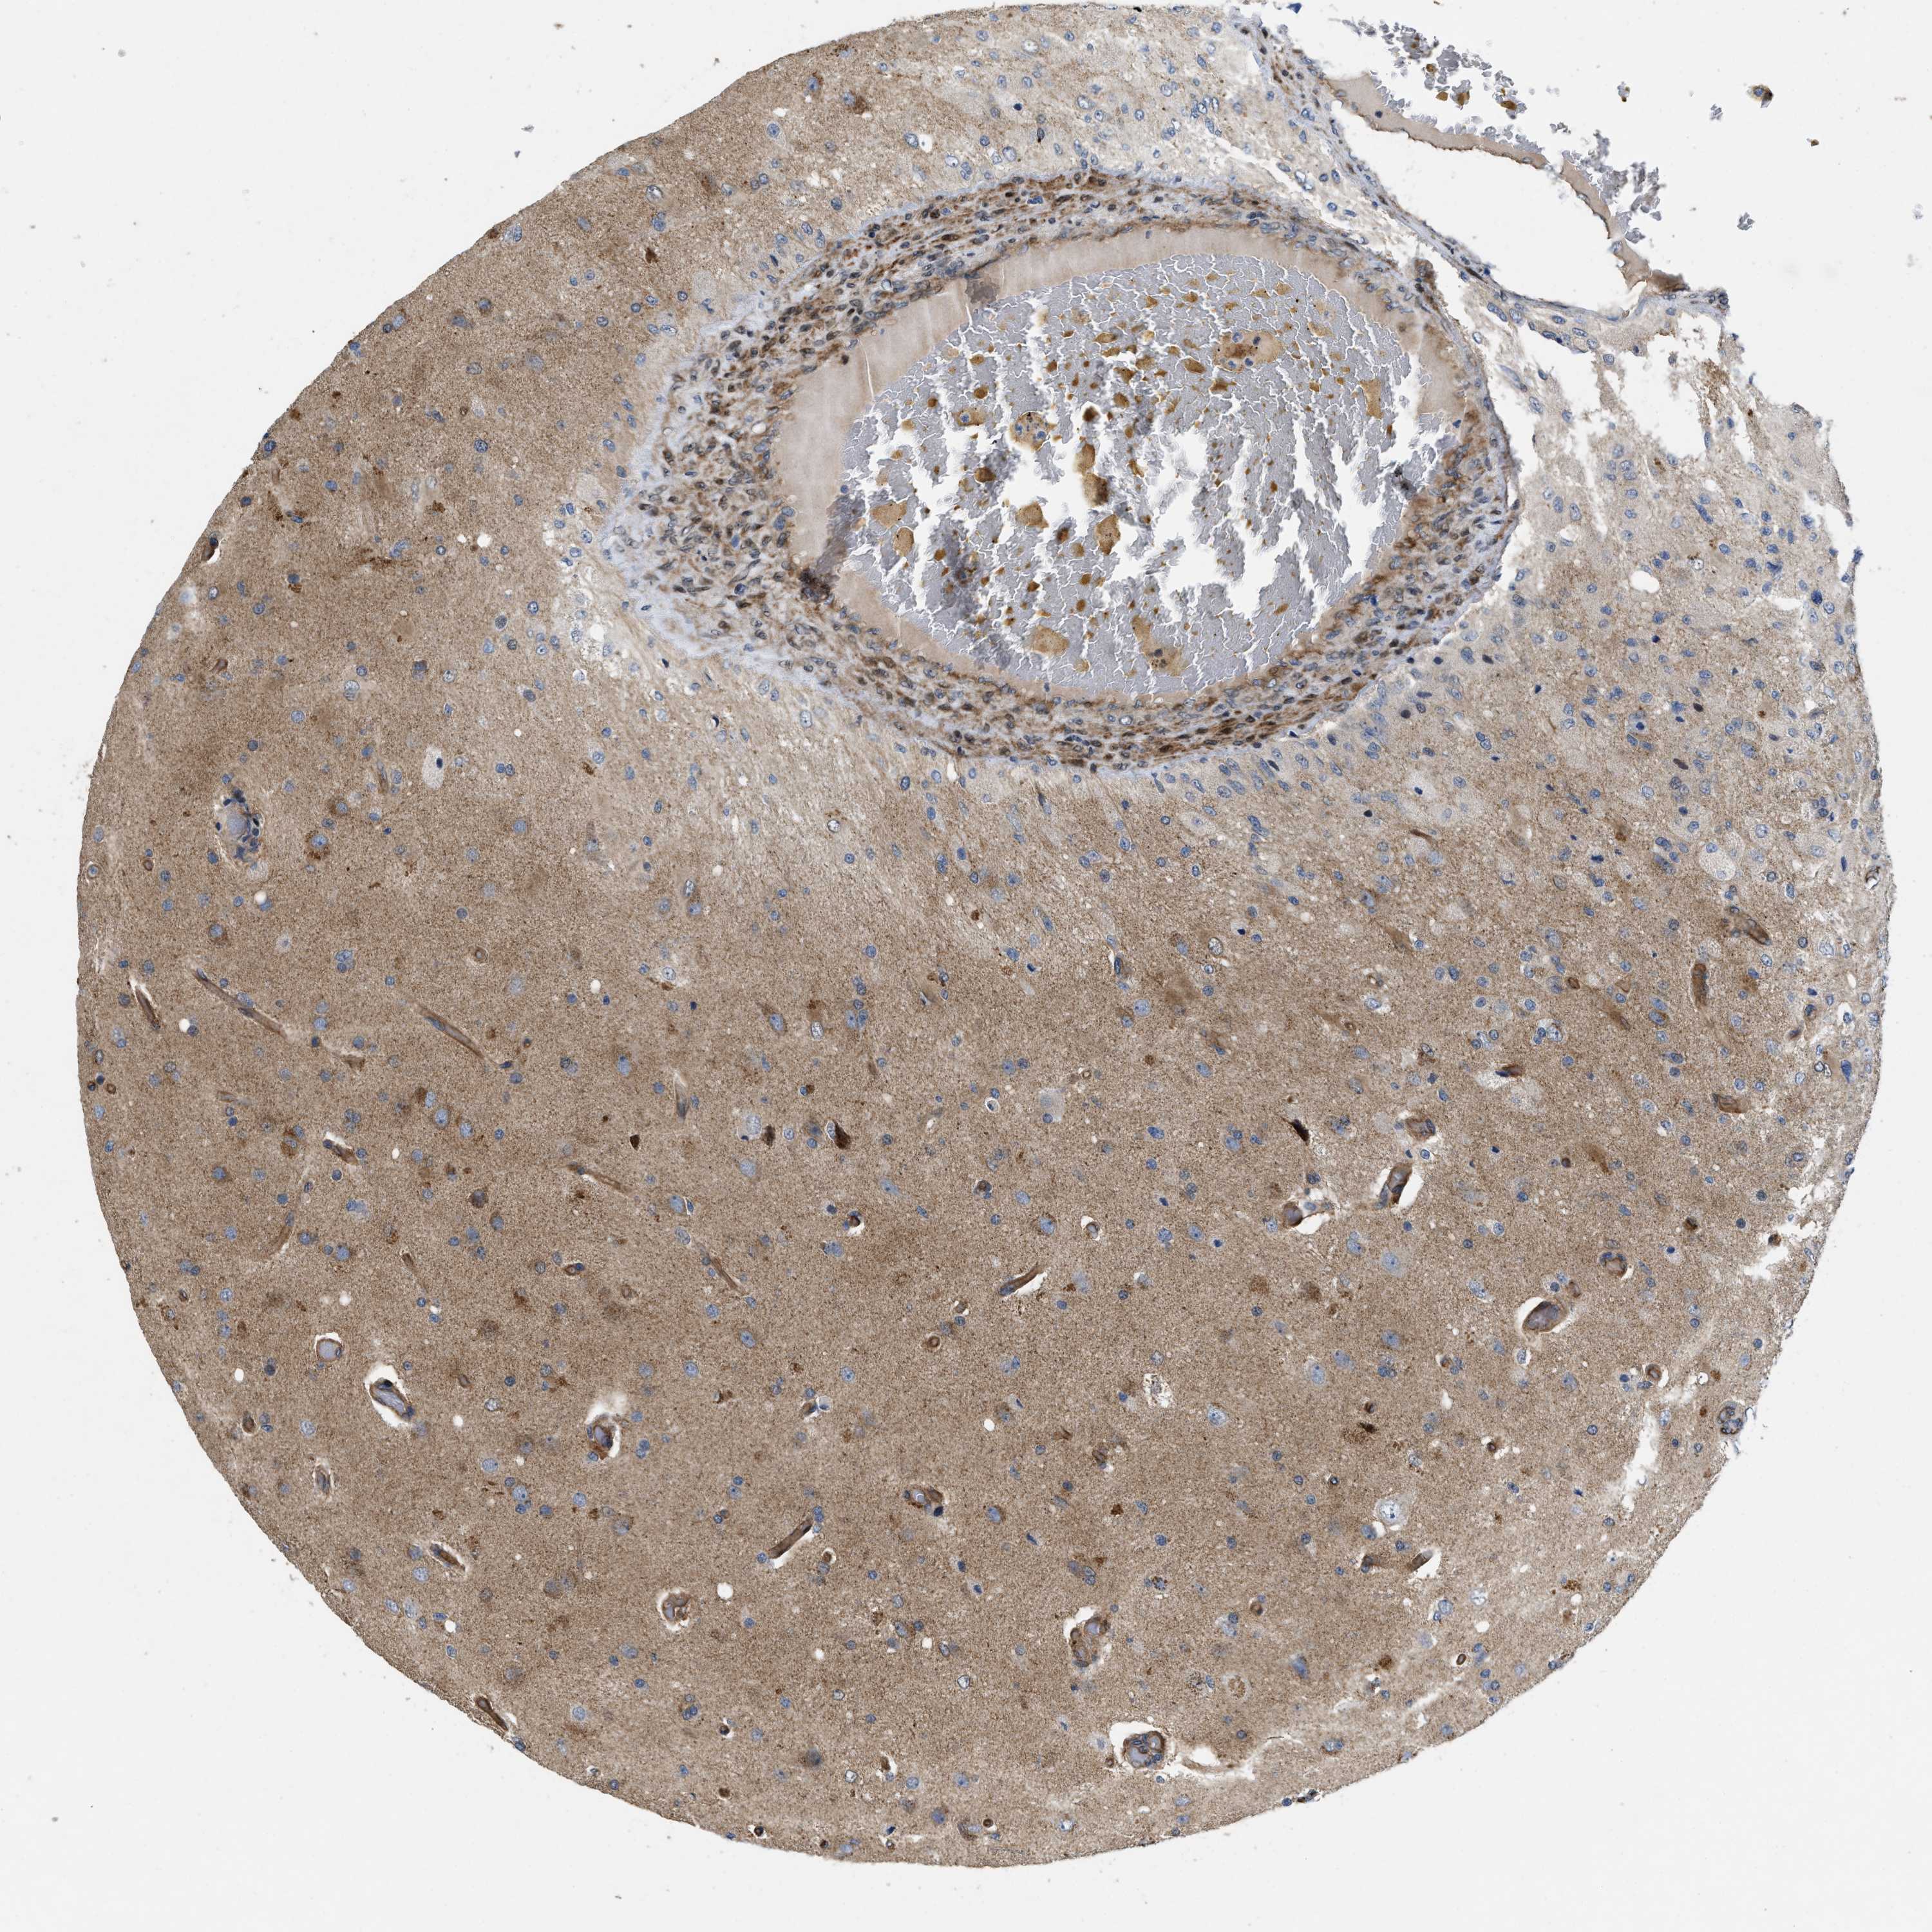

GLIOMA - Protein expressioni

A mouse-over function shows sample information and annotation data. Click on an image to view it in a full screen mode. Samples can be filtered based on level of antibody staining by selecting one or several of the following categories: high, medium, low and not detected. The assay and annotation is described here.

Note that samples used for immunohistochemistry by the Human Protein Atlas do not correspond to samples in the TCGA dataset.

Antibody stainingi

Antibody staining in the annotated cell types in the current human tissue is reported as not detected, low, medium, or high, based on conventional immunohistochemistry profiling in selected tissues. This score is based on the combination of the staining intensity and fraction of stained cells.

Each image is clickable and will lead to virtual microscopy that enables deeper exploration of all samples and also displays staining intensity scores, fraction scores and subcellular localization as well as patient and tissue information for each sample.

Antibody HPA013659

Antibody HPA015639

Staining

High

Medium

Low

Not detected

Intensity

Strong

Moderate

Weak

Negative

Quantity

>75%

75%-25%

<25%

None

Location

Nuclear

Cytoplasmic/membranous

Cytoplasmic/membranous,nuclear

Glioma, malignant, High grade

Glioma, malignant, Low grade